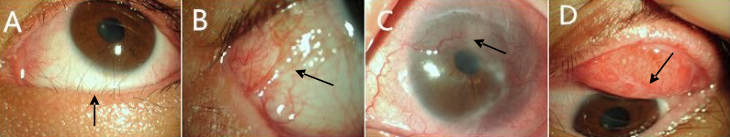

表现示例

A.角膜透明,无上皮点状混浊

B.角膜稍水肿,可见皮混浊

C.角膜荧光染色可见点状着染

D.睑结膜充血、水肿,可见伪膜形成